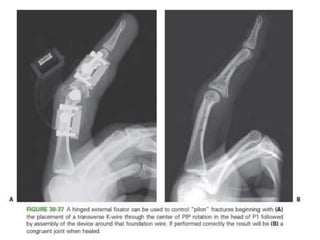

• Pilon fractures.

– Highly unstable,stifness of PIPJ.

– Dynamic traction / dorsal spring mechanism.

– The general principle is to establish a foundation at the center

of rotation in the head of P1.

– traction (adjustable or elastic) is applied along the axis of P2

to hold the metaphyseal component of the fracture out to

length

– while allowing early motion to remodel the articular surface

• #64 Dynamic traction / dorsal spring mechanism. The general principle is to establish a foundation at the center of rotation in the head of P1. From this foundation, traction (adjustable or elastic) is applied along the axis of P2 to hold the metaphyseal component of the fracture out to length while allowing early motion to remodel the articular surface